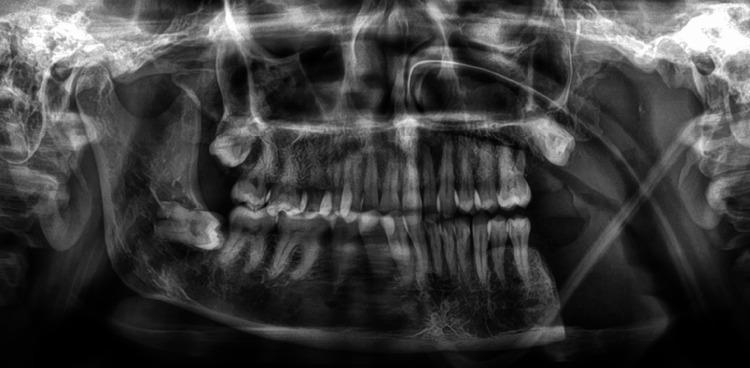

Primary intraosseous squamous cell carcinoma (PIOSCC) is a rare cancer that arises within the jaws, often linked to odontogenic cysts or tumors. Its prevalence is about 1-2.5% of all odontogenic tumors and presents a diagnostic challenge due to its similarity to other jaw lesions. A 46-year-old woman complained of persistent pain in the left back region of the lower jaw, numbness over the left side of the lower lip, and reduced mouth opening. The doctor revised the initial diagnosis of periapical infection due to ongoing symptoms and a non-healing socket. Radiological imaging revealed an osteolytic lesion in the left ramus of the mandible, prompting further investigation. A biopsy confirmed the diagnosis of IOSCC following histopathological examination after segmental mandibulectomy. The final diagnosis was primary intraosseous well-differentiated squamous cell carcinoma of the left mandible. PIOSCC, even though it is uncommon, should be included in the list of possible diagnoses for jaw problems, especially those that have unclear, bone-destroying X-ray features. Symptoms such as pain, swelling, and sensory disturbances, along with radiologic findings, may suggest a malignant odontogenic tumor. Histological evaluation is crucial for differentiation from other odontogenic tumors, including ameloblastic carcinoma. Radical surgery, often combined with neck dissection, is the management of choice. Postoperative radiotherapy or chemotherapy may be considered, though their role remains unclear. The five-year survival rate with PIOSCC ranges from 30% to 46%, indicating a typically dismal prognosis. PIOSCC is an uncommon, aggressive tumor with a poor prognosis. Early diagnosis and accurate histopathological examination are essential to differentiate it from other odontogenic carcinomas and improve patient outcomes.

原发性骨内鳞状细胞癌(PIOSCC)是一种罕见的癌症,发生于颌骨内,常与牙源性囊肿或肿瘤相关。其发病率约占所有牙源性肿瘤的1%-2.5%,由于与其他颌骨病变相似,给诊断带来了挑战。一名46岁女性主诉下颌左后区域持续疼痛、下唇左侧麻木以及张口受限。由于症状持续且拔牙创不愈合,医生修正了最初根尖感染的诊断。影像学检查显示下颌骨左支有溶骨性病变,促使进一步检查。在进行节段性下颌骨切除术后,经组织病理学检查,活检确诊为IOSCC。最终诊断为左下颌原发性骨内高分化鳞状细胞癌。PIOSCC尽管不常见,但应列入颌骨问题可能的诊断清单中,尤其是那些具有不明确的、骨质破坏的X线特征的病例。疼痛、肿胀和感觉障碍等症状,以及影像学表现,可能提示恶性牙源性肿瘤。组织学评估对于与其他牙源性肿瘤,包括成釉细胞癌进行鉴别至关重要。根治性手术,通常联合颈部清扫术,是首选的治疗方法。术后可考虑放疗或化疗,但其作用仍不明确。PIOSCC的五年生存率为30%至46%,表明预后通常不佳。PIOSCC是一种罕见的侵袭性肿瘤,预后不良。早期诊断和准确的组织病理学检查对于将其与其他牙源性癌进行鉴别并改善患者预后至关重要。